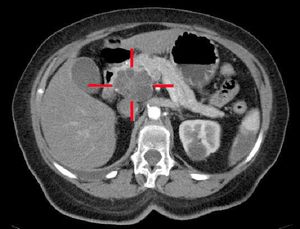

의학 영상 기술인 컴퓨터 단층 촬영(CT 스캔) 및 내시경 초음파 (EUS)는 진단을 확인하고 종양의 외과적 절제 가능성("절제 가능성")을 결정하는 데 사용된다.[4] 조영 CT 스캔에서 췌장암은 정상 췌장에서 보이는 빠른 소실이나 만성 췌장염에서 보이는 지연된 소실과 달리 점진적으로 증가하는 조영제 섭취를 일반적으로 보여준다.[56] 자기 공명 영상 및 양전자 방출 단층 촬영도 사용될 수 있으며,[3] 자기 공명 담관 췌장 조영술이 일부 경우에 유용할 수 있다.[54] 복부 초음파는 덜 민감하며 작은 종양을 놓치지만, 간으로 전이된 암과 복강 내 체액 축적(복수)을 식별할 수 있다.[4] 다른 기술 전에 빠르고 저렴한 첫 번째 검사에 사용할 수 있다.[70]

; CT

: 비조영 검사에서는 임상적으로 유용한 정보가 부족하기 때문에 일반적으로 동적 조영을 실시한다. 췌장암은 혈류가 부족한 경우가 많으므로, 조영 초기(동맥상)에는 췌 실질보다 조영 불량 영역으로 묘사된다. 조영 후기(평형상)에는 췌 실질과 비슷한 정도의 조영 효과를 나타내어 불분명해진다. 한편, 췌내분비 종양은 혈류가 풍부하기 때문에 조영 초기부터 강하게 증강된다. 또한, 주변으로의 침윤 소견이나 림프절 전이, 원격 전이의 평가도 가능하다.